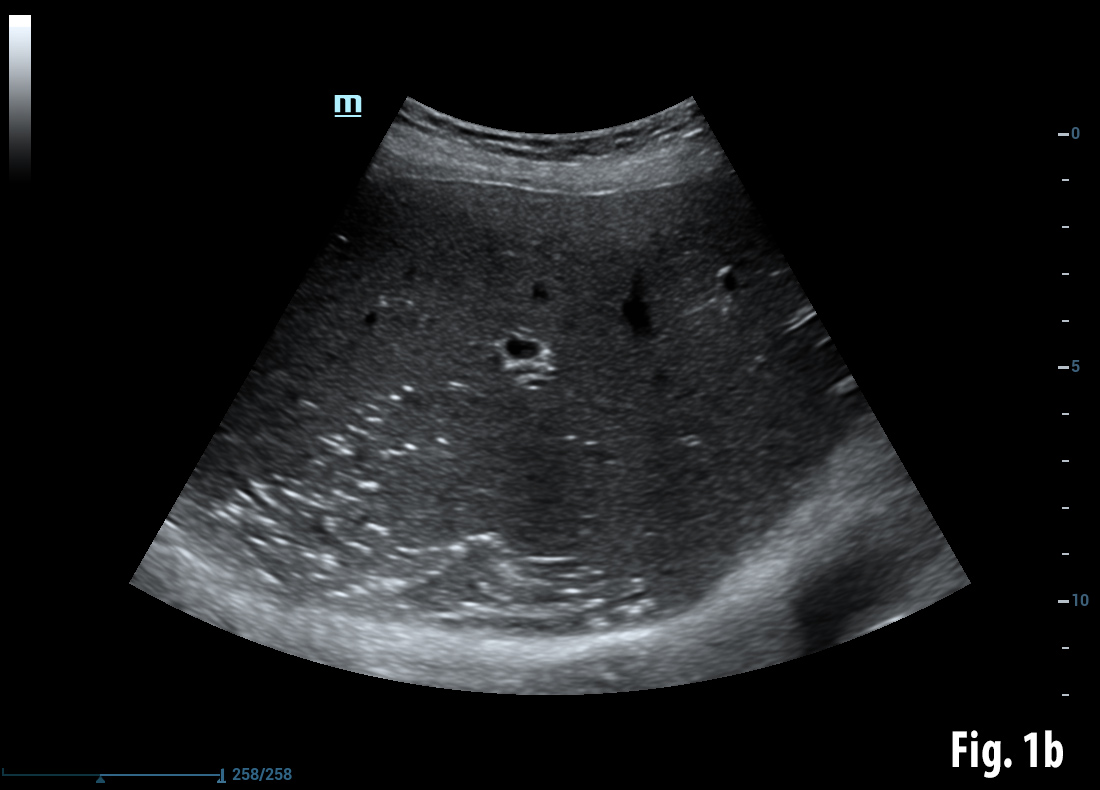

Conventional B-mode ultrasound revealed a mass lesion in the gallbladder region (a) and air bubbles within the liver (aerobilia) (b). Contrast enhanced ultrasound showed arterial enhancement as a sign of neoplasia (c). Endoscopy revealed a gallstone in the duodenal bulb (d). Elastography showed stiff tissue (blue) supportive of neoplasia (e). Details of elastography are explained in the EFSUMB guidelines on elastography [(1, 2)].

![Bouveret syndrome</br> [Apr 2016]](http://s834315022.websitehome.co.uk/wp-content/uploads/2020/11/cotm_april2016-fig1b.jpg)